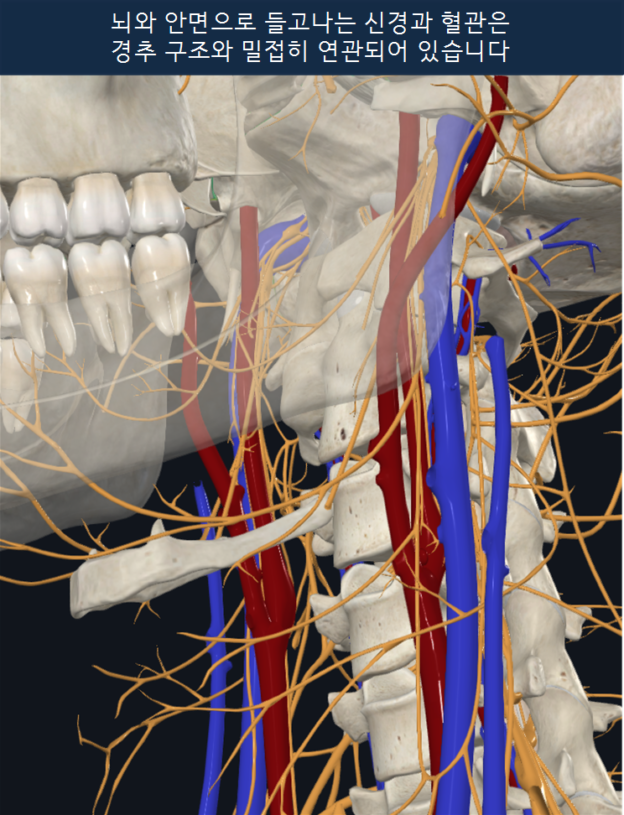

브레인포그 증상을 만들어내는 배경에는 두개경추 영역의 구조와 기능의 병리적 변화가 숨어있다.

이런 신체의 병리적 변화를 오스테오파시에서 체성기능부전(somatic dysfunction)이라고 한다. 뼈, 근육, 관절, 인대, 근막, 신경, 혈관 등으로 구성된 체성 구조에서 움직임, 긴장도, 위치, 혈류, 감각 및 반사 조절 등의 기능적 조화가 무너진 상태를 의미한다.

두개경추 영역에 다양한 방식으로 나타나는 체성기능부전은 곧 브레인포그에 숨겨진 신체적 원인이 된다.

이 70대 여성분처럼 두개골이 한쪽으로 밀려서 이탈된 상태라면 척추동맥을 통한 뇌줄기와 두개내로의 혈류 공급이 충분히 유지될 수 있을까?

이와함께 상부경추 C1, C2가 한쪽으로 굽혀져 치우쳐 있고 움직임이 매우 제한되어 마치 시멘트로 굳어진 것 같은 상태이다. 뇌줄기가 공간적 압박없이 편하게 있을 수 있을까? 미주신경, 교감신경절, 혈관, 림프 등이 밀집해있는 좁은 공간 역시 이런 스트레스로부터 자유로울 수 있을까? (브레인포그·이인증 환자를 위한 원인탐색과 치료: 두개경추불안정)

- 뇌간과 척수 – 각성상태, 자세균형, 수면주기 조절, 호흡, 심박수, 혈압 등 불안정

- 척추동맥 – 뇌로가는 혈류저하

- 뇌척수액 순환 – 후두하영역의 뇌척수액 펌핑장애

- 뇌림프 배출 – 정체로 인해 뇌척수액 혼탁, 뇌 활력 저하

- 미주신경과 상부교감신경절 – 자율신경실조 증상

- 두개내압 증가 – 머리 속 압박감, 앞머리 무거움, 안구 압박감

- 뇌신경과 목혈관신경집

두개경추불안정은 이런 중요 기능들에 동시다발적인 장애를 일으킬 수 있고 브레인포그의 숨겨진 원인이 될 수 있다.